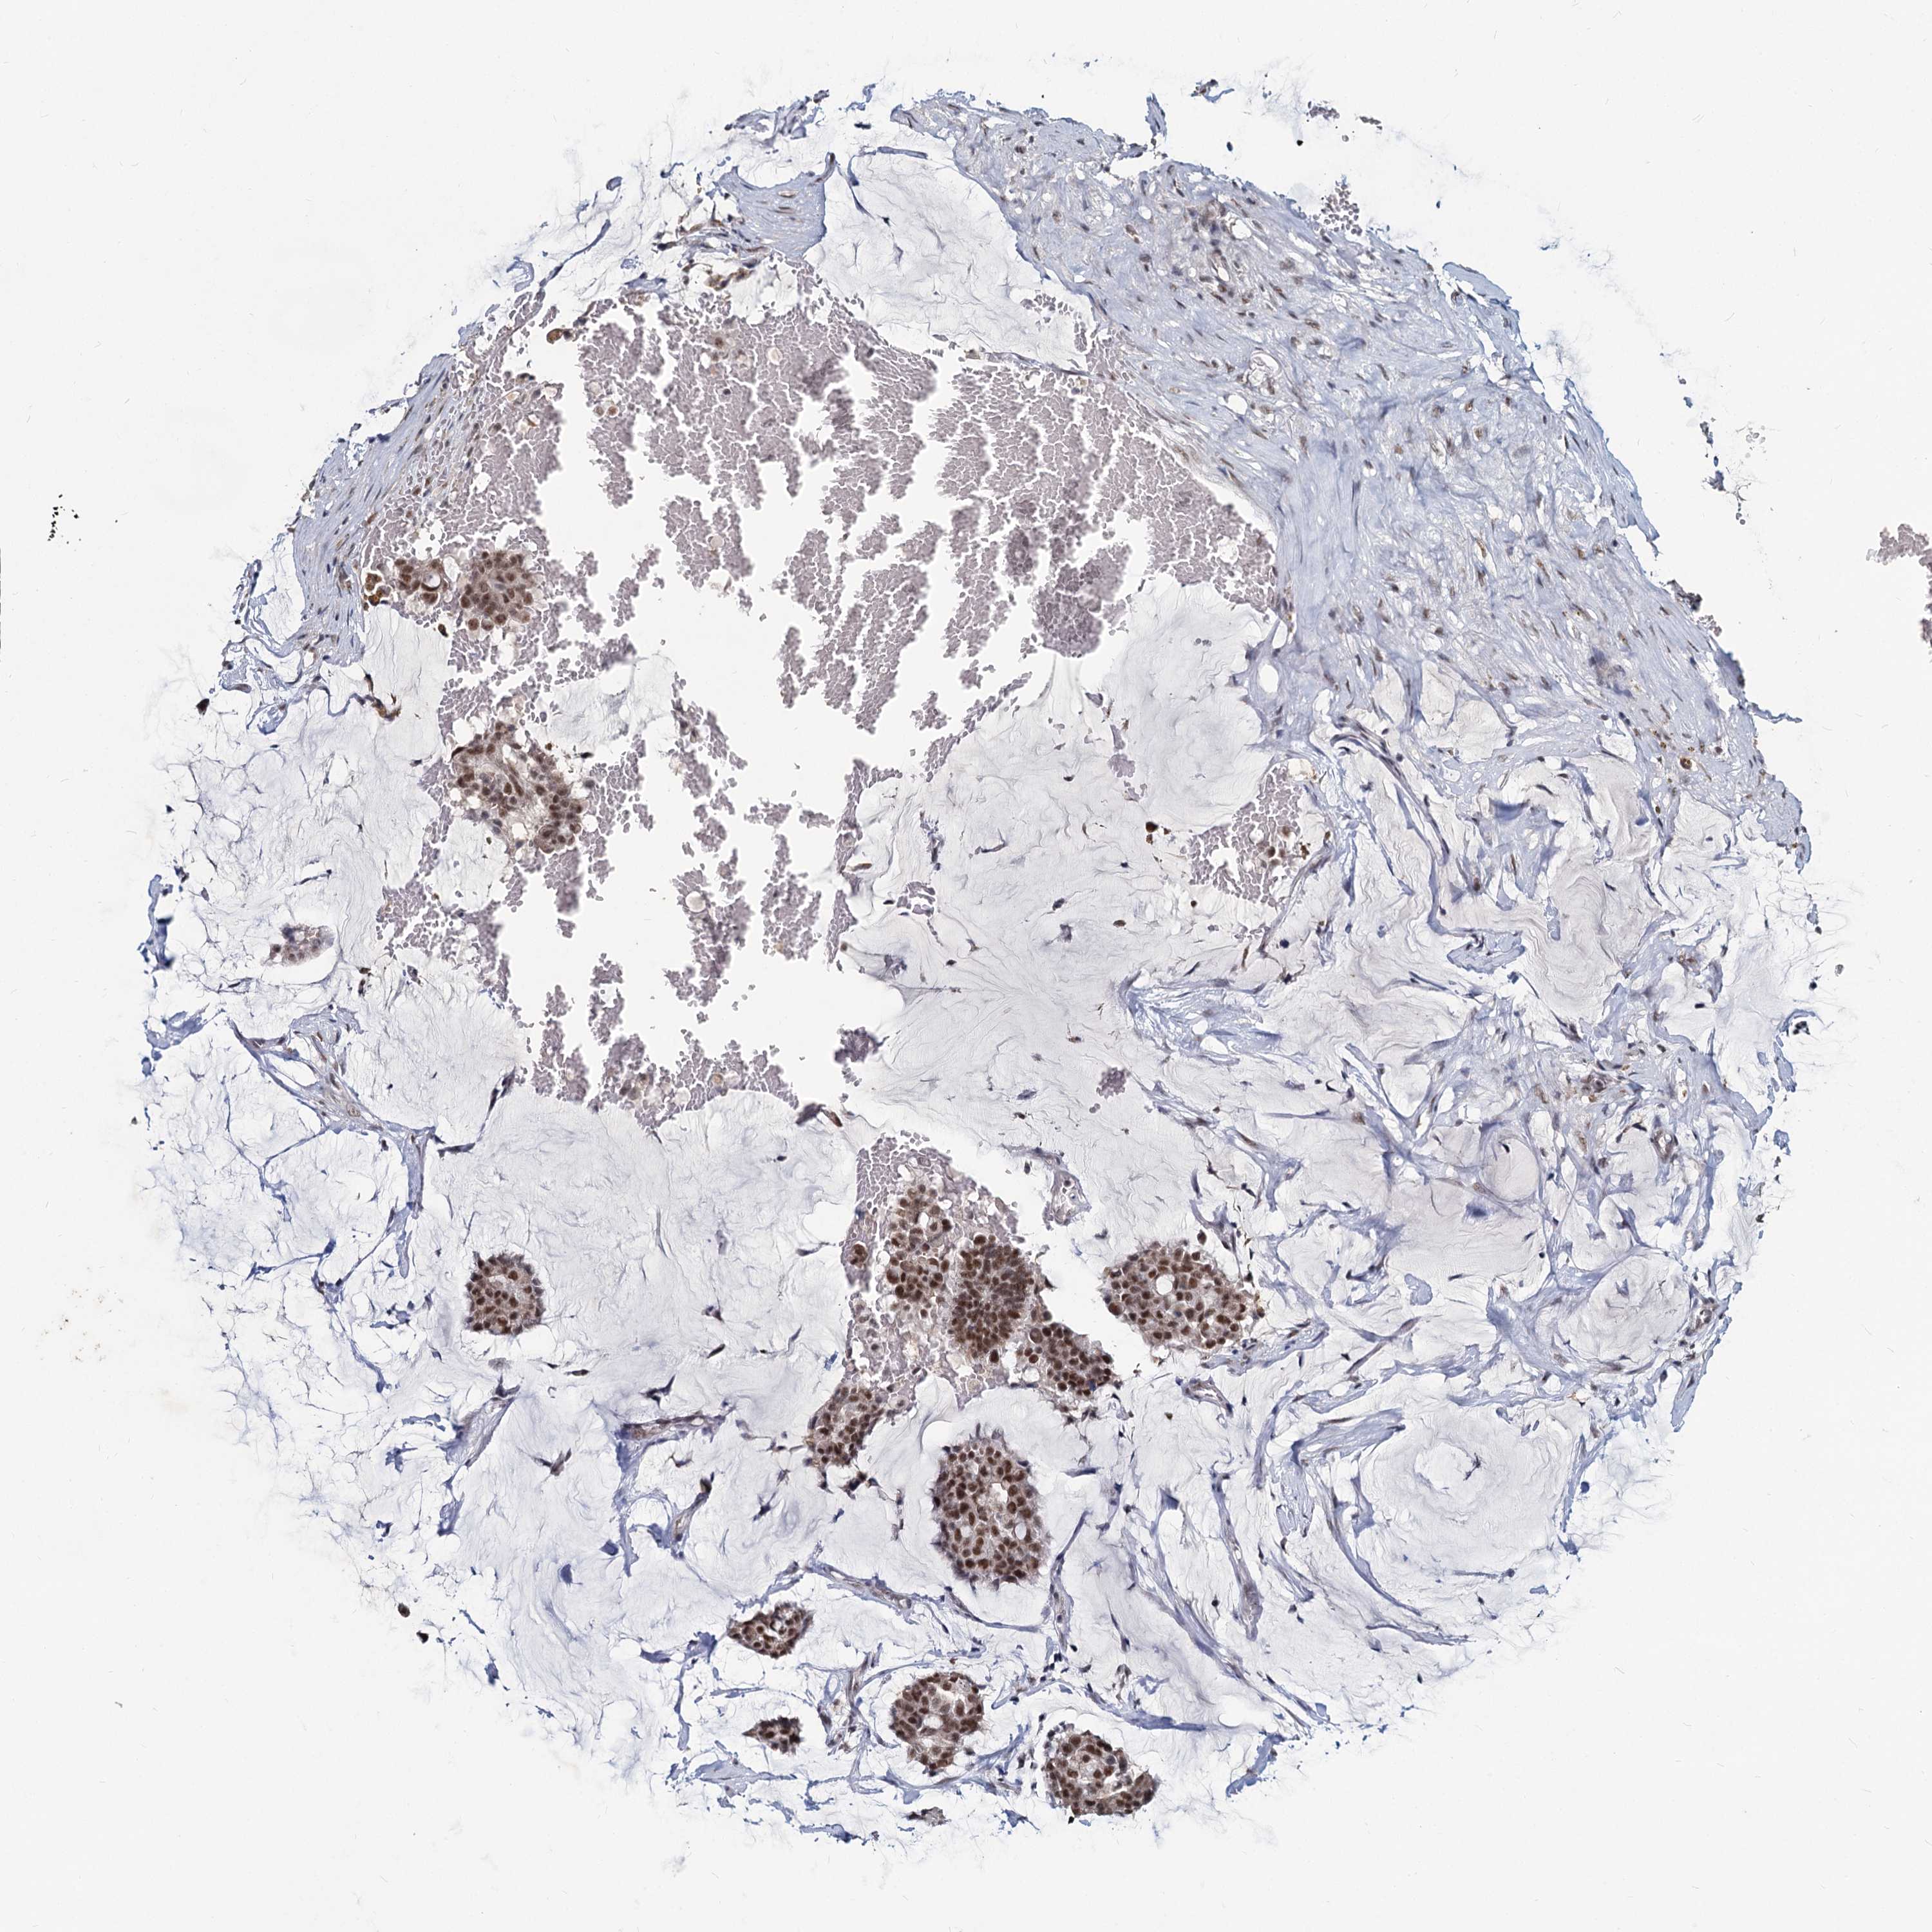

CANCER BREAST CANCER Show tissue menu

BRCA TCGA BRCA VALIDATION PROTEIN EXPRESSION